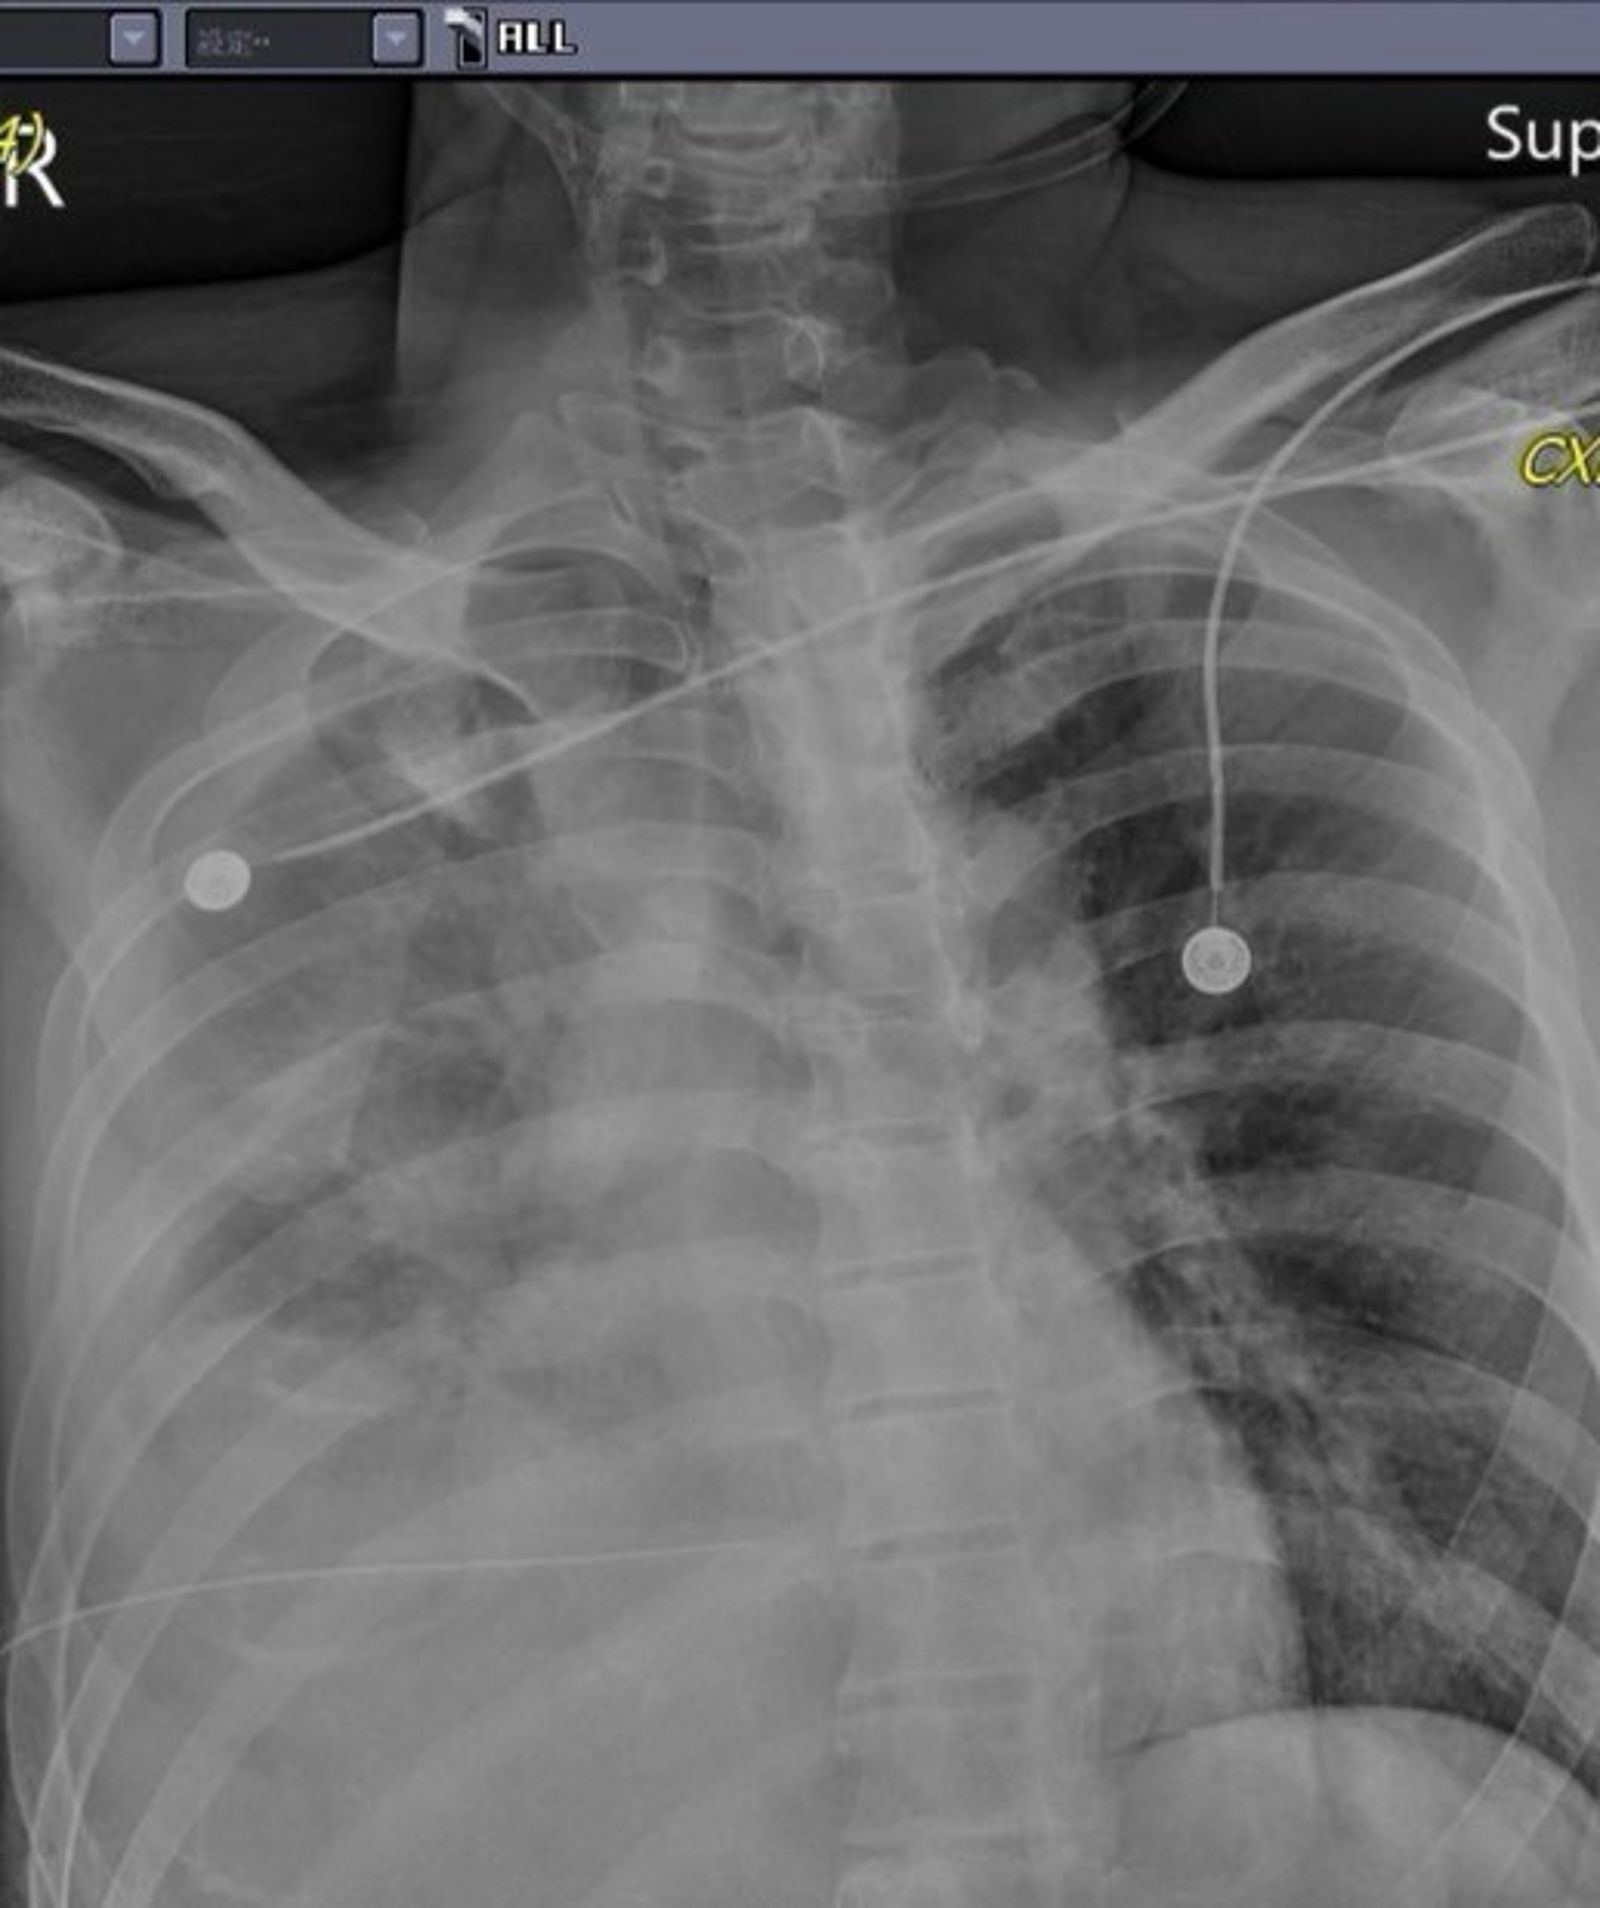

苗栗2日發生持刀攻擊事件,其中50歲林姓男子被送往大千醫院搶救,外科部長馮啟彥就分享,當天下午被急診找去看林姓受害人時,「真的是傻眼,是怎樣的深仇大恨?」馮啟彥說,本來以為只有氣血胸,但是置放胸管後,仍有持續性出血現象,因為利刃穿刺很深,導致橫膈膜及肝臟都有破裂及大量出血,因此當晚由胸腔外科及一般外科醫師聯手一起介入手術,所幸3日上午已經能夠清醒的與大家致意。